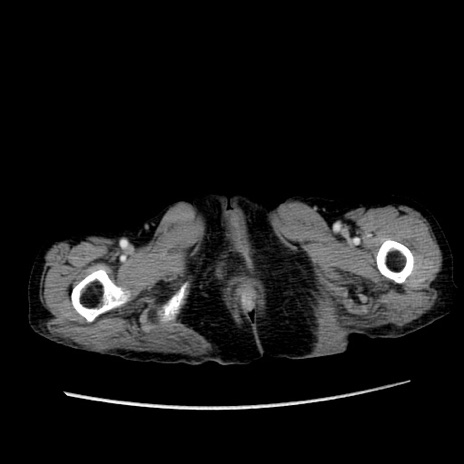

症例25(横断像)

【症例】80歳代女性

【主訴】胸のつかえ感

【現病歴】約9時間前に食後から胸のつかえた感じあり、嘔吐あり、来院。

【既往歴】胃癌(全摘)、胆摘、虫垂炎

【身体所見】心窩部に圧痛あり、反跳痛なし。

【データ】WBC 5700、CRP 0.05